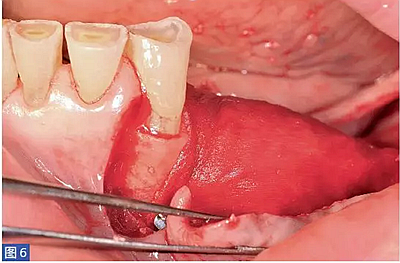

圖6:(左側(cè))病例1. 用鈦釘固定膜。

圖7:(右側(cè))病例1. 術(shù)后6 個月的再生組織。